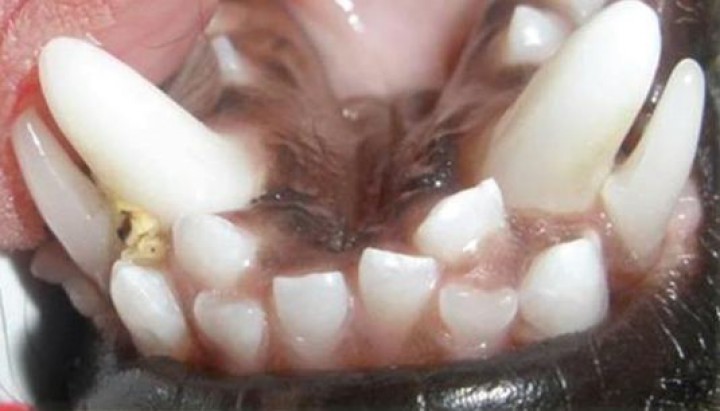

Persistencia de la dentadura decidua (Fig. 2)

Un diente deciduo se considera persistente cuando el diente permanente ya está presente en la cavidad oral, no siendo necesario que este último haya erupcionado completamente.[ Hobson P. Extraction of retained primary canine teeth in the dog. J Vet Dent, 2005; 22 (2):132-137. ]

<p>Persistencia de dentadura decidua. Apréciense los dientes caninos deciduos inferiores, vestibulares a los dientes caninos definitivos, y los incisivos definitivos centrales que han erupcionado linguales a los deciduos.</p>

Persistencia de dentadura decidua. Apréciense los dientes caninos deciduos inferiores, vestibulares a los dientes caninos definitivos, y los incisivos definitivos centrales que han erupcionado linguales a los deciduos.

La etiología más frecuente es la erupción incorrecta del diente permanente, que no ejerce suficiente presión en la raíz del diente de leche y, por lo tanto, no se reabsorbe.[ Hobson P. Extraction of retained primary canine teeth in the dog. J Vet Dent, 2005; 22 (2):132-137. , Brook AN. Pathology in the pediatric patient. En: Niemiec B: Small Animal Dental, Oral and Maxillofacial Disease. Manson Publishing. London 2010; 90-123. ] Esta es una teoría clásica de la erupción pero existen otras causas que también participan.

Se produce principalmente en razas “Toy” y pequeñas, pero puede ocurrir en cualquier raza de perros y también en gatos.[ Hobson P. Extraction of retained primary canine teeth in the dog. J Vet Dent, 2005; 22 (2):132-137. , Brook AN. Pathology in the pediatric patient. En: Niemiec B: Small Animal Dental, Oral and Maxillofacial Disease. Manson Publishing. London 2010; 90-123. ] Los dientes que se afectan con mayor frecuencia son los caninos, seguidos de los incisivos y por último, los premolares.[ Harvey CE, Emily PP. Small Animal Dentistry, Mosby, St.Louis. 1993. ] La consecuencia de esta anomalía es la predisposición a la enfermedad periodontal y la aparición de traumatismos a nivel gingival, palatino o dentario. A veces incluso se produce pulpitis en la dentición permanente.[ Hale FA. Juvenile Veterinary Dentistry. Vet Clin North Am: Small Anim Pract. 2005; (35):789-817. [PubMed] ]

Se debe hacer diagnóstico diferencial con los dientes supernumerarios, dentadura decidua persistente sin el correspondiente diente permanente y coronas malformadas.[ Brook AN. Pathology in the pediatric patient. En: Niemiec B: Small Animal Dental, Oral and Maxillofacial Disease. Manson Publishing. London 2010; 90-123. ]

Todos los dientes de leche deben ser exodonciados tan pronto como sea posible.[ Hobson P. Extraction of retained primary canine teeth in the dog. J Vet Dent, 2005; 22 (2):132-137. , Harvey CE, Emily PP. Small Animal Dentistry, Mosby, St.Louis. 1993. ] La radiografía dental previa a la extracción es esencial. Estos procedimientos pueden ser difíciles, ya que en ocasiones existe reabsorción y anquilosis de la raíz del diente de leche. Además, debemos evitar dañar el desarrollo del diente permanente. Es bastante común la fractura de la raíz, si esto ocurre, debemos proceder a su extracción, aunque para ello sea necesario realizar un abordaje quirúrgico.[ Hobson P. Extraction of retained primary canine teeth in the dog. J Vet Dent, 2005; 22 (2):132-137. , Brook AN. Pathology in the pediatric patient. En: Niemiec B: Small Animal Dental, Oral and Maxillofacial Disease. Manson Publishing. London 2010; 90-123. ]